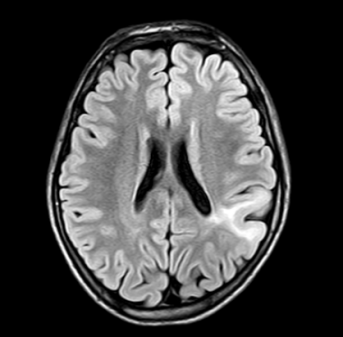

吴建珩副主任团队收治小浩后,迅速开展病因排查。头颅磁共振、视频脑电图和PET-CT都指向了左顶叶的一处病灶——皮质发育不良。郑州大学五附院神经外科二病区李培栋主任迅速召开癫痫多学科会诊MDT,会诊意见指出该处病灶即为癫痫的起源灶,符合癫痫灶切除术的指征,但该病变紧邻语言和肢体运动的功能区,存在一定的手术风险。